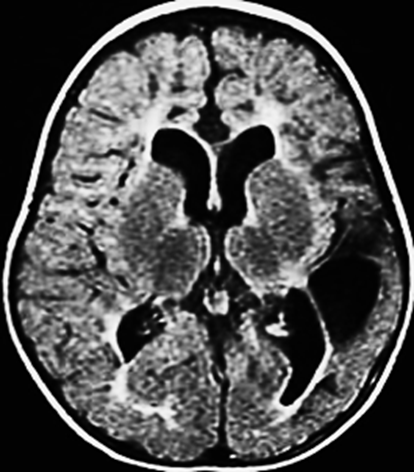

MRI (preferred modality):

• Periventricular leukomalacia (PVL): Seen in preterm infants; indicates white matter damage.

• Cerebral atrophy

• Delayed myelination

• Basal ganglia injury: Especially in term infants with HIE.

• Congenital malformations: e.g., schizencephaly, lissencephaly.

CT Scan:

• May detect calcifications or hemorrhages, but is less sensitive than MRI for white matter injury.

MRI findings correlate with motor and cognitive outcomes.